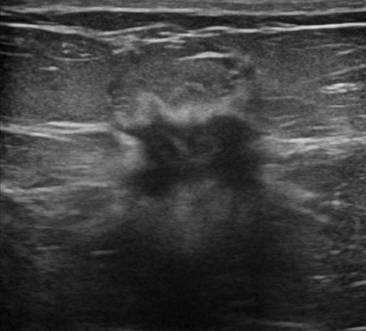

Ung thư vú

Ung thư vú - Ảnh 3

» Thông tin: Nữ giới – 56 tuổi.

» Lâm sàng: Khối tuyến vú.